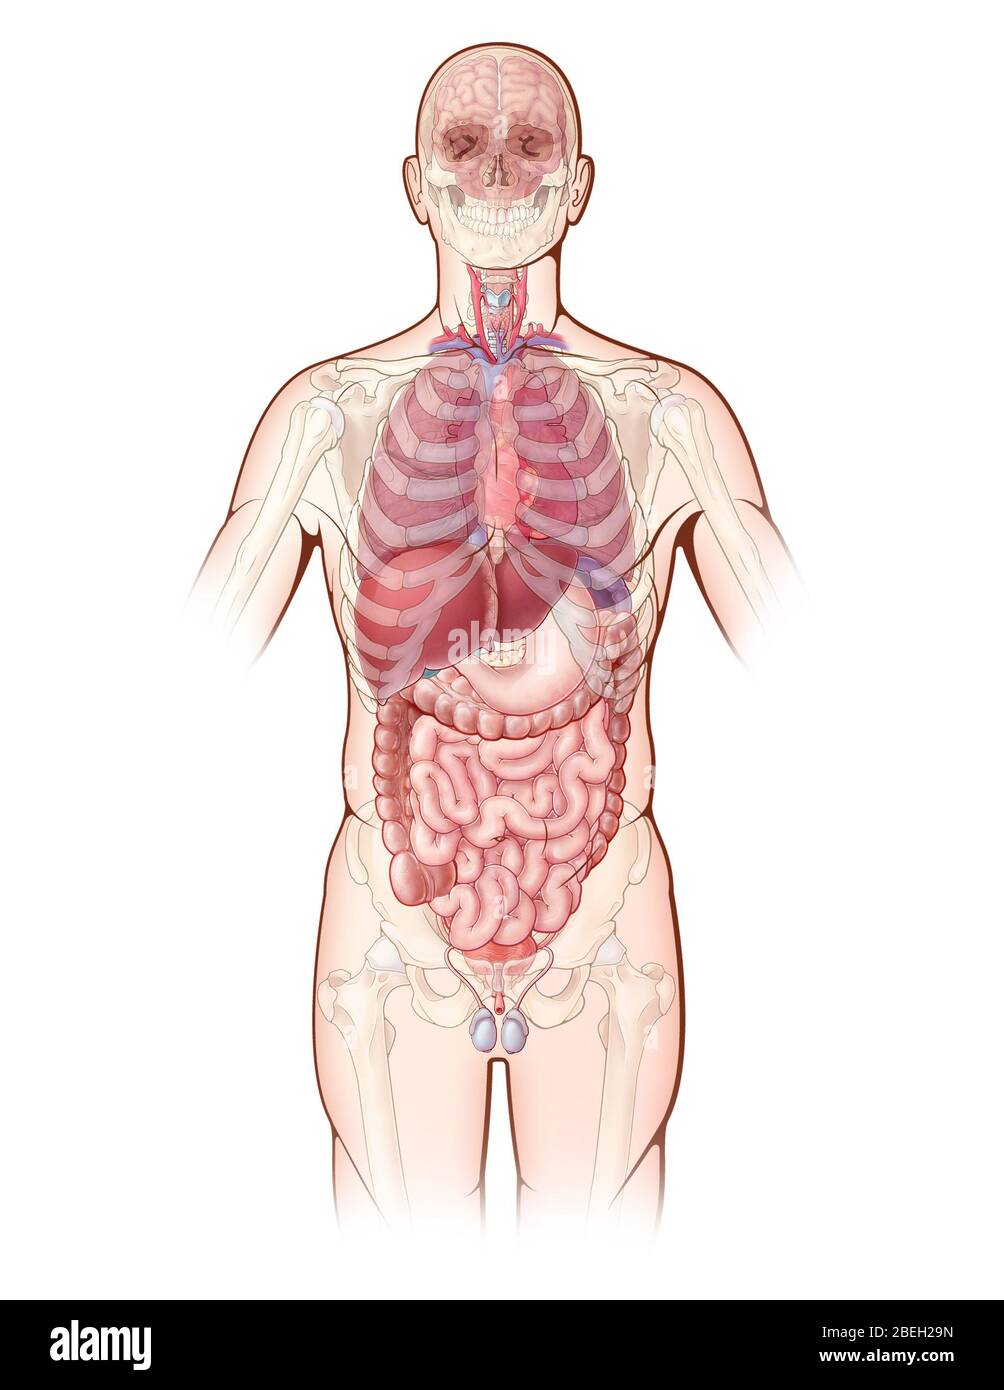

An illustration depicting the major organs in the human body, as well as a ghosted view of the bones of the skeleton. Stock Photohttps://www.alamy.com/image-license-details/?v=1https://www.alamy.com/an-illustration-depicting-the-major-organs-in-the-human-body-as-well-as-a-ghosted-view-of-the-bones-of-the-skeleton-image353187569.html

An illustration depicting the major organs in the human body, as well as a ghosted view of the bones of the skeleton. Stock Photohttps://www.alamy.com/image-license-details/?v=1https://www.alamy.com/an-illustration-depicting-the-major-organs-in-the-human-body-as-well-as-a-ghosted-view-of-the-bones-of-the-skeleton-image353187569.htmlRM2BEH29N–An illustration depicting the major organs in the human body, as well as a ghosted view of the bones of the skeleton.